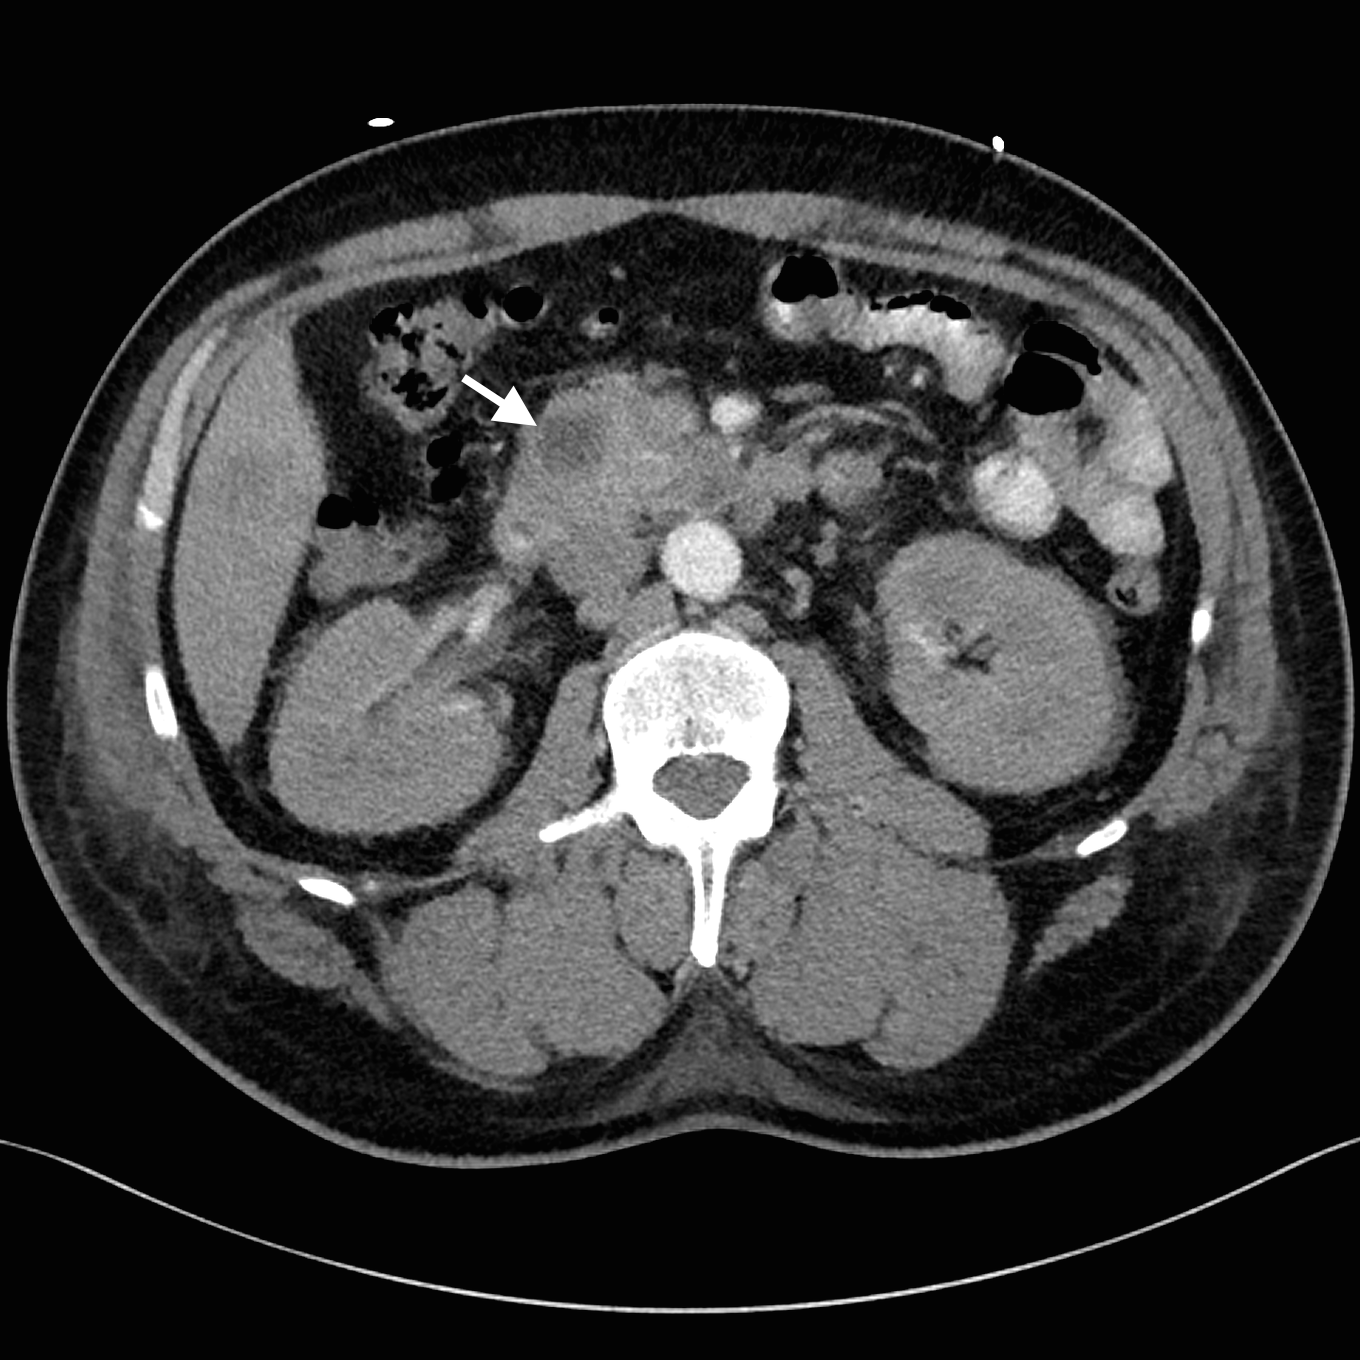

Despite adequate fluid replacement, the patient remained oliguric and developed deteriorating uraemia, so that haemodialysis was initiated. This facilitated further investigation with contrast-enhanced triple-phase hepatic CT, which confirmed a 25 × 23 × 17 mm heterogeneous head of pancreas mass, together with multiple hypodense liver lesions (Figure). Ultrasound-guided fine-needle aspiration biopsy of a liver lesion was performed. The cytological profile and immunohistochemical characteristics of the biopsy sample were consistent with metastatic adenocarcinoma, probably of pancreatic origin.